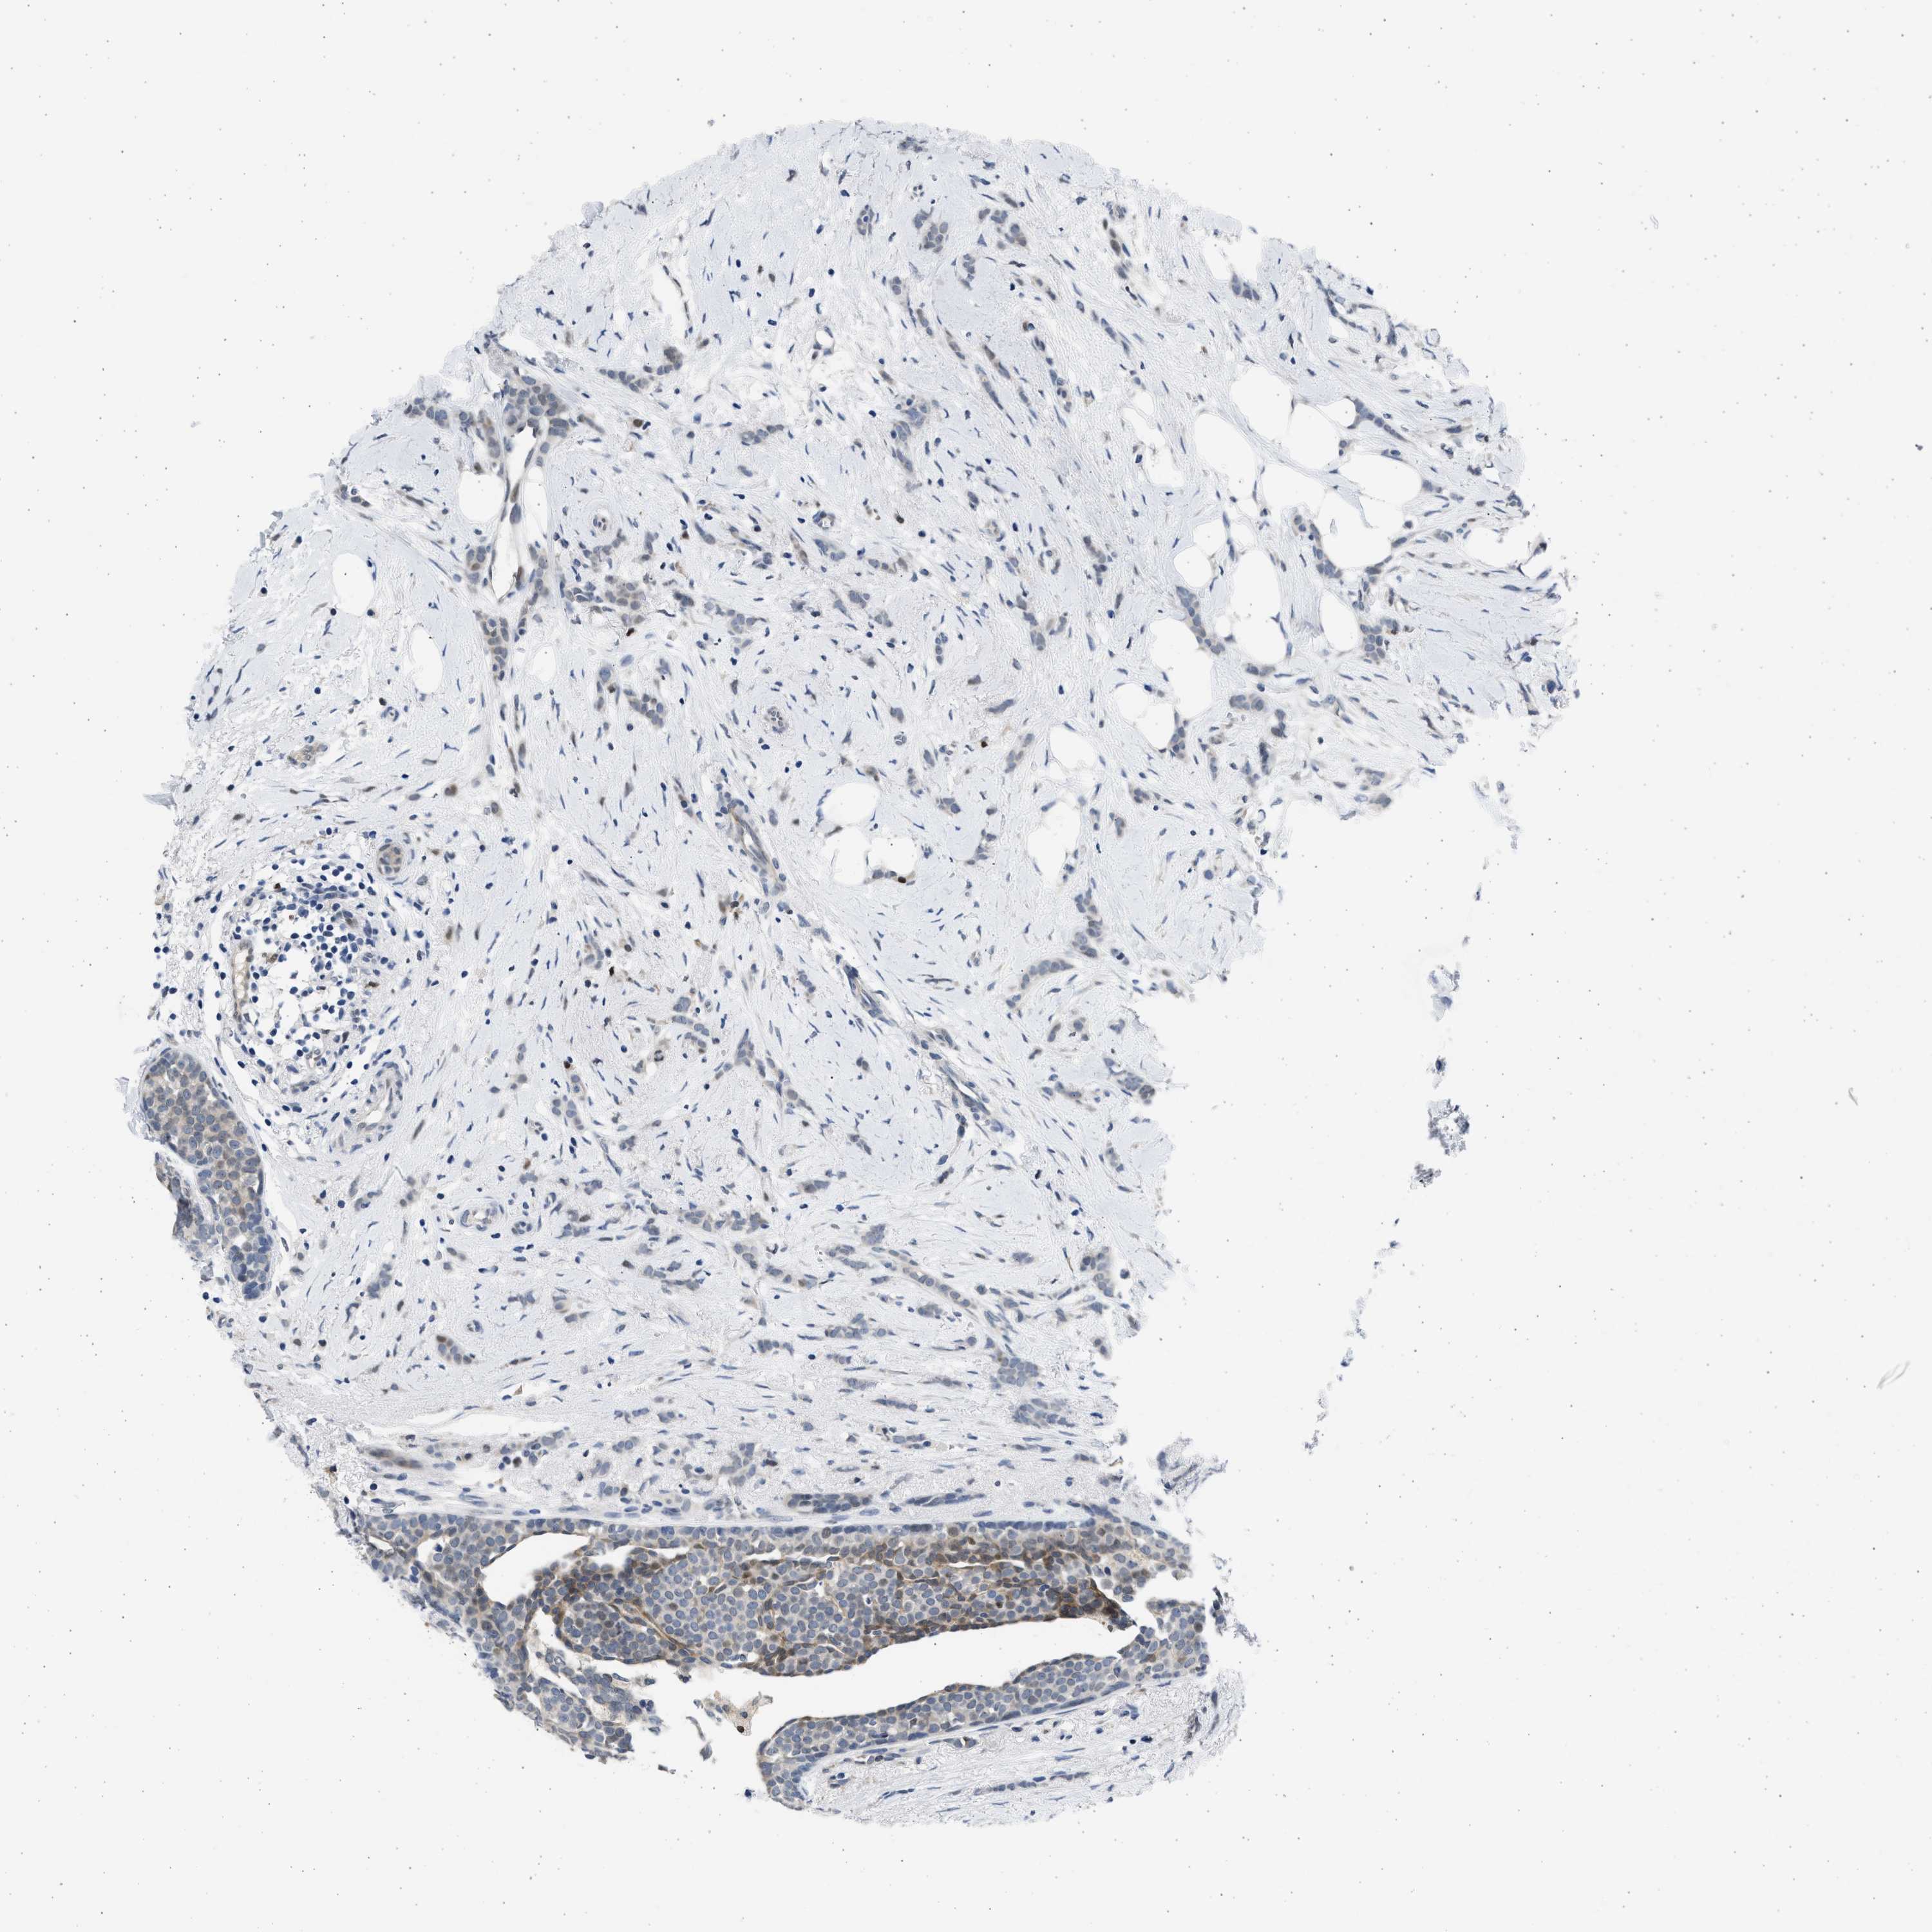

CANCER BREAST CANCER Show tissue menu

BRCA TCGA BRCA VALIDATION PROTEIN EXPRESSION